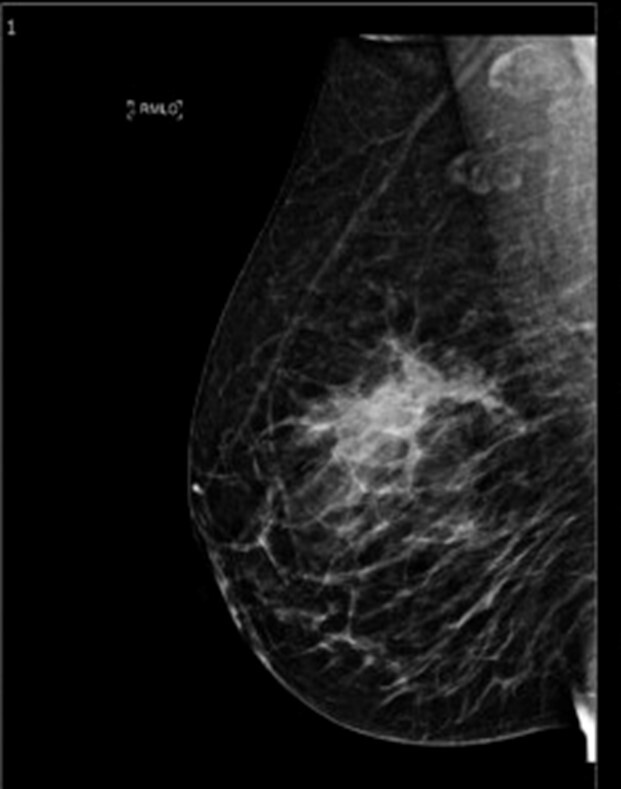

Mammographie du sein G : Échographie du sein G :

Question 10 - Concernant ces résultats, vous notez que (une ou plusieurs réponses exactes) :

Les deux examens sont en faveur d’une lésion maligne.

La mammographie et l’échographie retrouvent un nodule spiculé de 41 mm du quadrant supéro-interne du sein gauche.